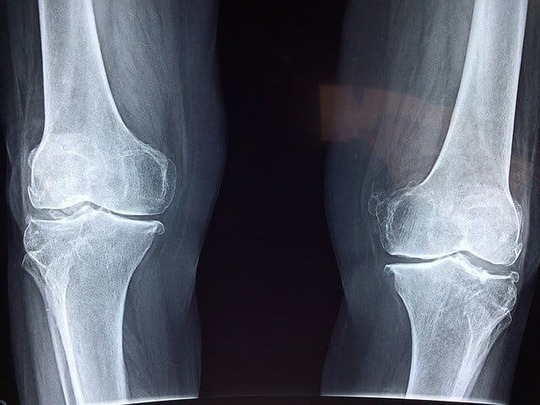

足のしびれ、痛み